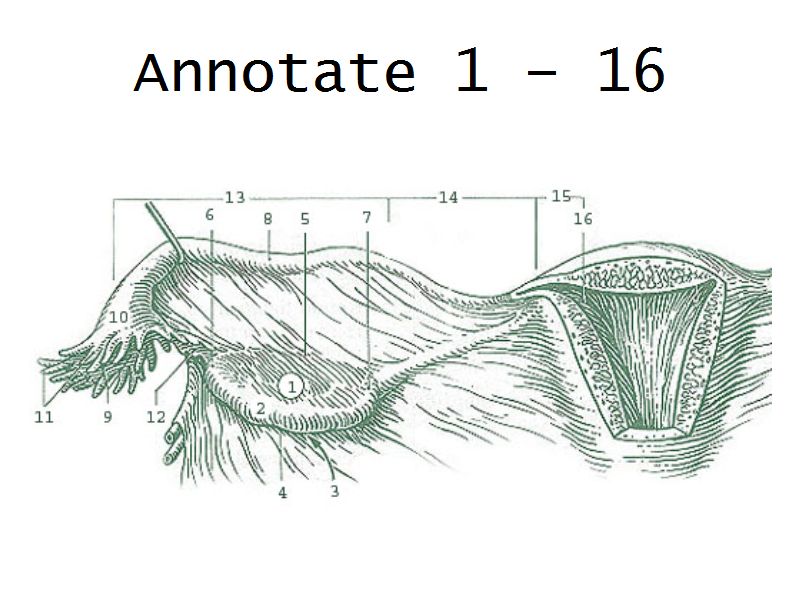

Tuba uterina

Slide 97

Also:

OviductFallopian tube

Uterine tube

Tuba uterina

- Muscular tube

- Most frequent site of fertilization

- Conveys zygote to uterus

- Four regions

- Three layers

Four regions

- Infundibulum

- Ampulla

- Usual site of fertilization

- Isthmus

- Pars interstitialis

- Passes through wall of uterus

Three layers

- Mucosa

- Muscular layer

- Serosa